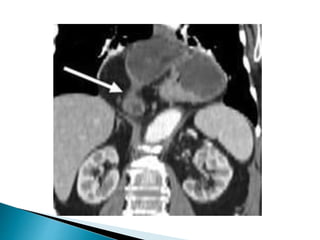

Ba contrast enema

contrast-filled rectum

illustrates the "bird's beak"

sign (white arrow),

corresponding to the

luminal narrowing at the

site of sigmoid obstruction.

This is the characteristic

presentation of a sigmoid

volvulus